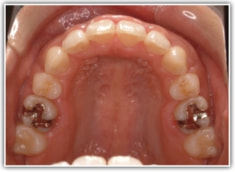

治療前